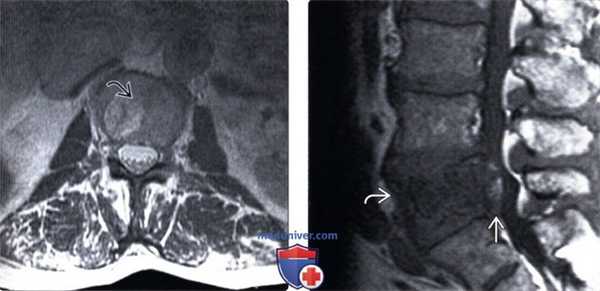

(Слева) Сагиттальный срез, Т1-ВИ с КУ: хорошо выраженная вертикальная исчерченность тела позвонка, характерная для гемангиомы. Определяются признаки экстраоссального распространения опухоли в вентральный отдел эпидурального пространства.

(Справа) Аксиальный срез, Т1-ВИ с КУ: накапливающее контраст образование в заднем отделе тела грудного позвонка и задних элементах с выраженным эпидуральным распространением образования и сдавлением спинного мозга. Ключом к диагнозу (в данном случаев агрессивной гемангиомы с экстраоссальным распространением) является картина утолщенных костных трабекул, характеризующихся низкой интенсивностью сигнала.

(Слева) Аксиальный срез, Т2-ВИ поясничного позвонка: четко ограниченное гиперинтенсивное образование. Мелкие гипоинтенсивные вкрапления соответствуют утолщенным костным трабекулам, которые хорошо видны на КТ.

(Справа) Сагиттальный срез, Т1-ВИ: бедная жировой тканью гемангиома L5 позвонка, характеризующаяся диффузной гипоинтенсивностью сигнала тела позвонка Также визуализируется вентральный эпидуральный компонент, сдавливающий дуральный мешок, характеризующийся смешанной интенсивностью сигнала жировой ткани и мягких тканей, представляющий собой экстраоссальный компонент гемангиомы.